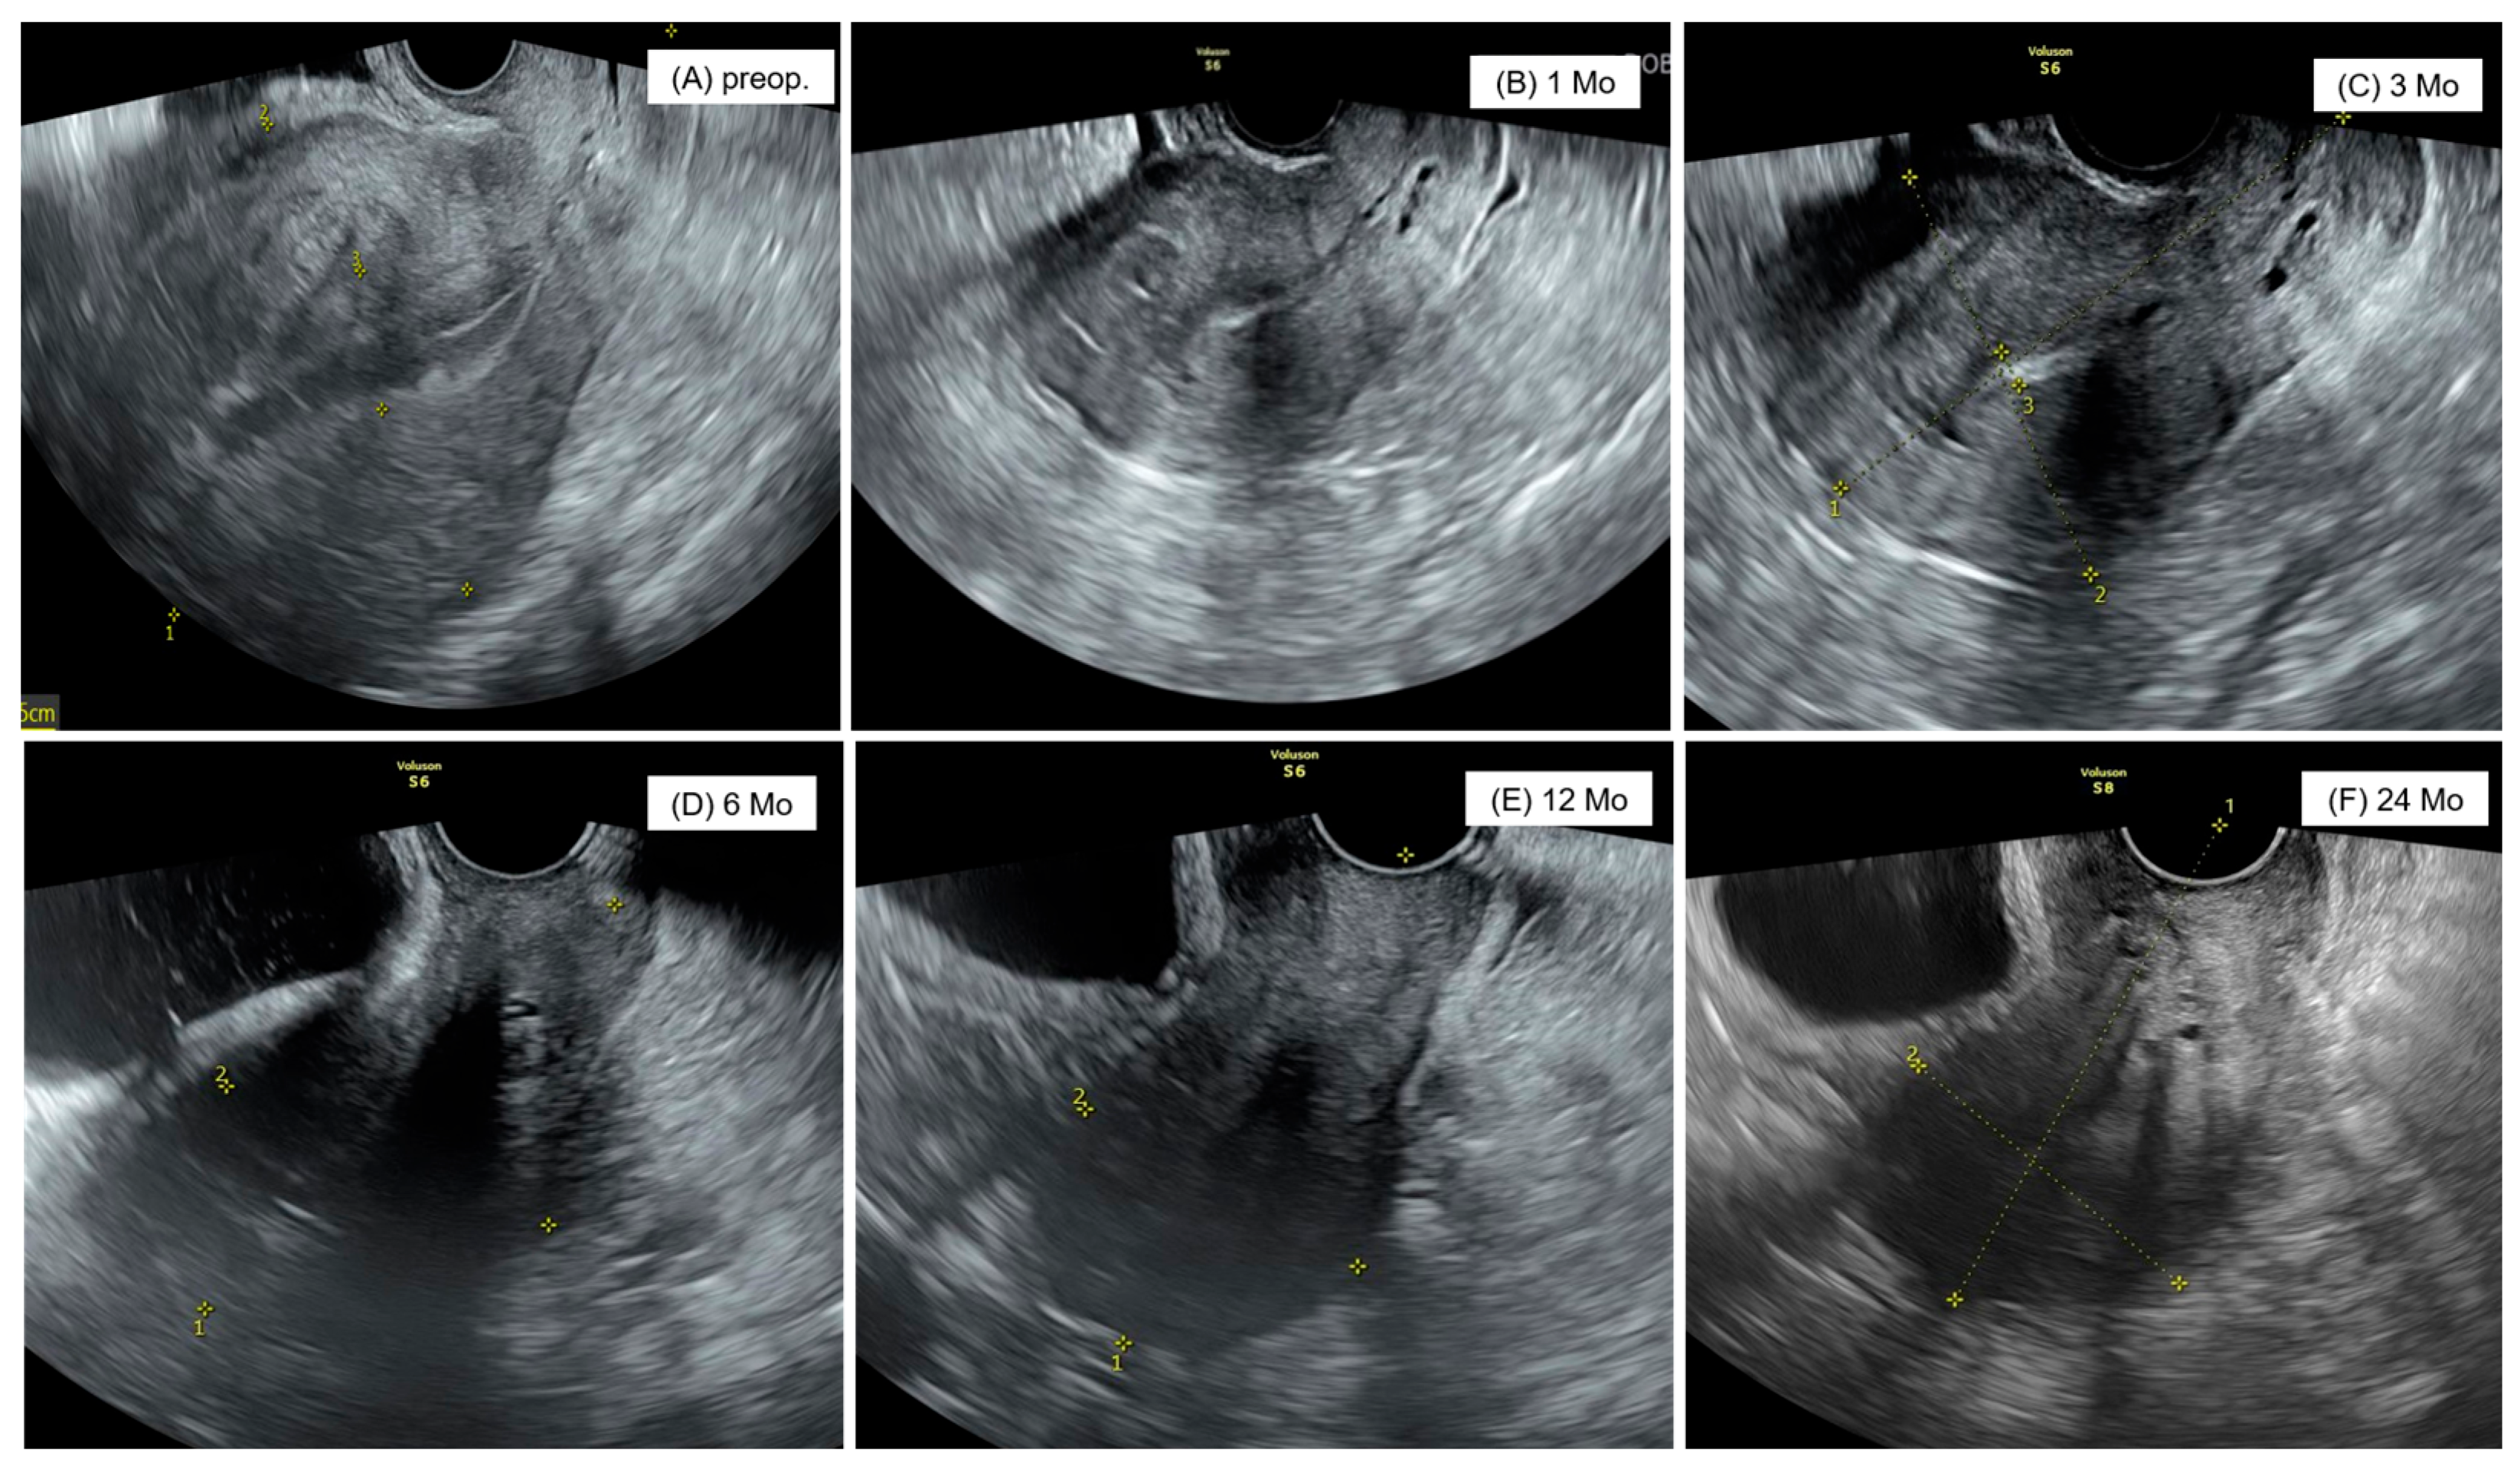

| Preoperative longitudinal length of uterus (cm) | 10.04 ± 1.90 | 10.32 ± 10.56 | 0.76 |

| Preoperative volume of uterus (gm) | 332.55 ± 193.97 | 263.09 ± 144.53 | 0.00 |

| Postoperative state 1 Mo later | |||

| Longitudinal length of uterus (cm) | 7.02 ± 1.02 | 8.51 ± 4.41 | 0.00 |

| Weight of uterus (gm) | 83.09 ± 40.20 | 136.48 ± 75.76 | 0.00 |

| Postoperative state 3 Mo later | |||

| Longitudinal length of uterus (cm) | 6.61 ± 0.97 | 7.26 ± 1.28 | 0.00 |

| Volume of uterus (gm) | 72.09 ± 32.32 | 94.45 ± 66.12 | 0.00 |

| Postoperative state 6 Mo later | |||

| Longitudinal length of uterus (cm) | 6.49 ± 1.04 | 7.58 ± 1.64 | 0.00 |

| Volume of uterus (gm) | 64.54 ± 42.36 | 108.52 ± 79.84 | 0.00 |

| Postoperative state 12 Mo later | |||

| Longitudinal length of uterus (cm) | 6.61 ± 1.18 | 7.73 ± 1.31 | 0.00 |

| Volume of uterus (gm) | 63.27 ± 35.39 | 109.95 ± 78.97 | 0.00 |

| Postoperative state 24 Mo later | |||

| Longitudinal length of uterus (cm) | 6.38 ± 1.09 | 7.80 ±1.47 | 0.00 |

| Volume of uterus (gm) | 58.11 ± 31.12 | 128.55 ± 143.16 | 0.00 |